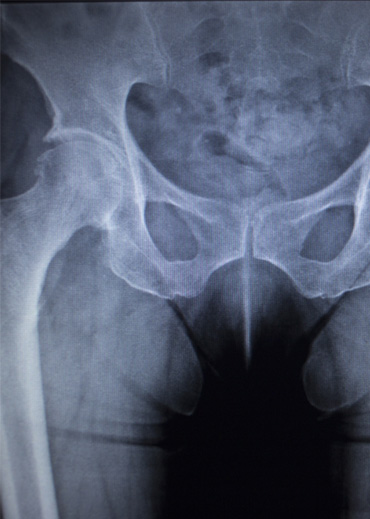

Dr. Vijay Kumar Sohanlal is an esteemed orthopedic surgeon, specializing in joint replacement. Renowned for his expertise in robotic knee replacement , Total knee & hip replacement , revision knee & revision hip replacement, he has helped numerous patients regain mobility and improve their quality of life. He has trained extensively under some of the world’s leading orthopaedic specialists across Australia, Germany, and Mumbai. Dr. Sohanlal’s skills enable him to perform bilateral knee joint replacements in a single sitting, minimizing recovery time and hospital stays for his patients.